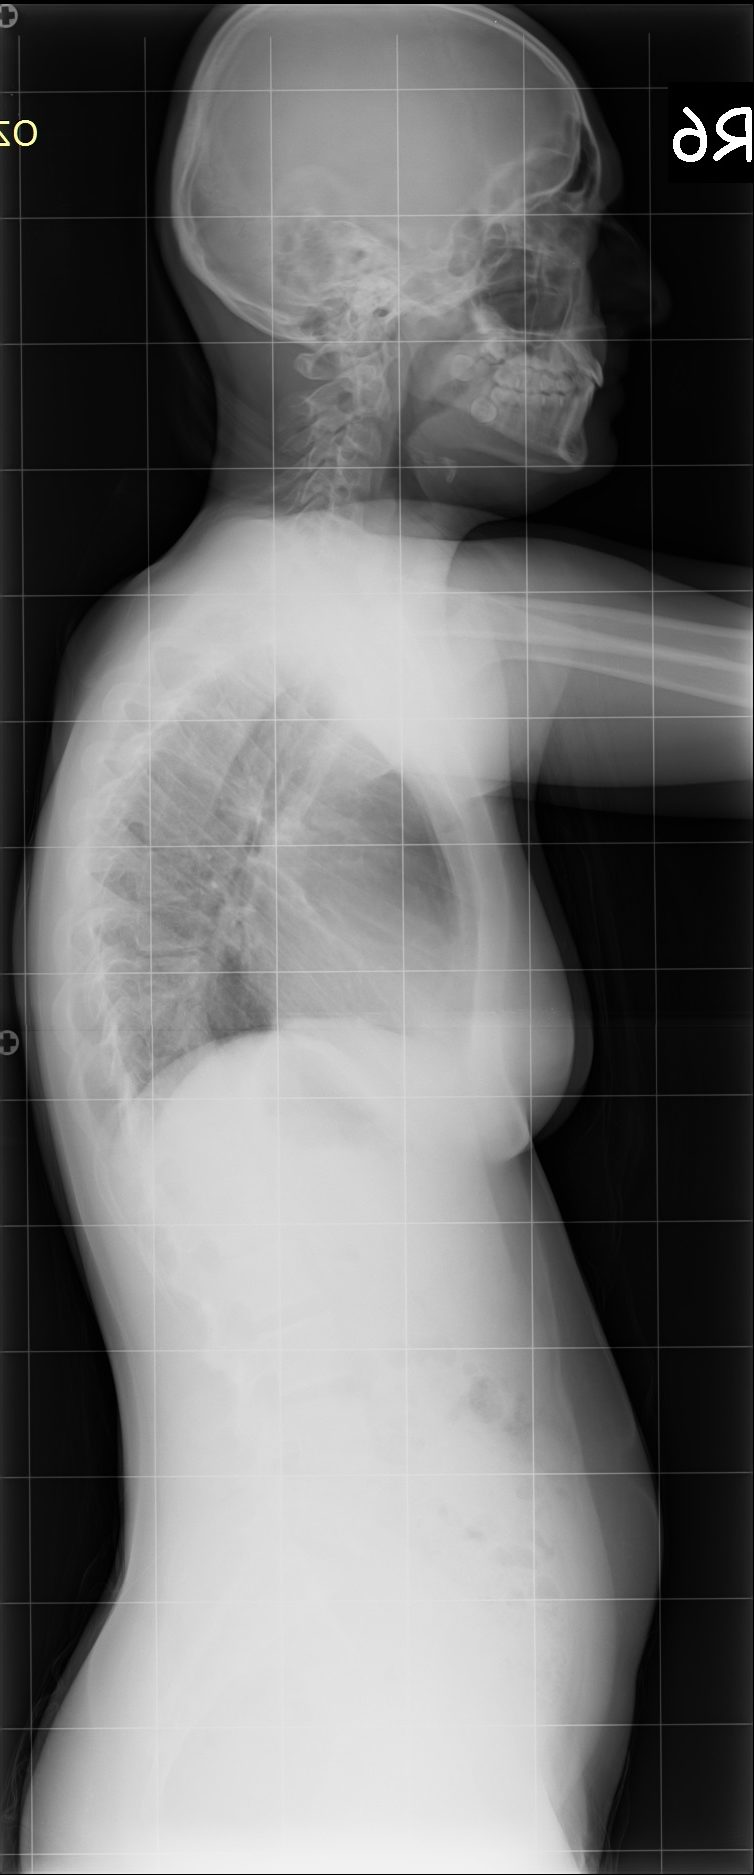

16 Yaşında Kadın Hasta

Ameliyat Öncesi